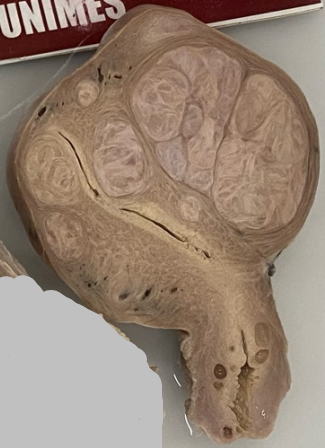

-Órgão: Rim.

-Descrição: Tamanho muito aumentado, pequenos

cistos externamente, que se evidenciam na superfície de corte, consistência esponjosa e múltiplos cistos.

-Diagnóstico: Doença policística renal da infância.